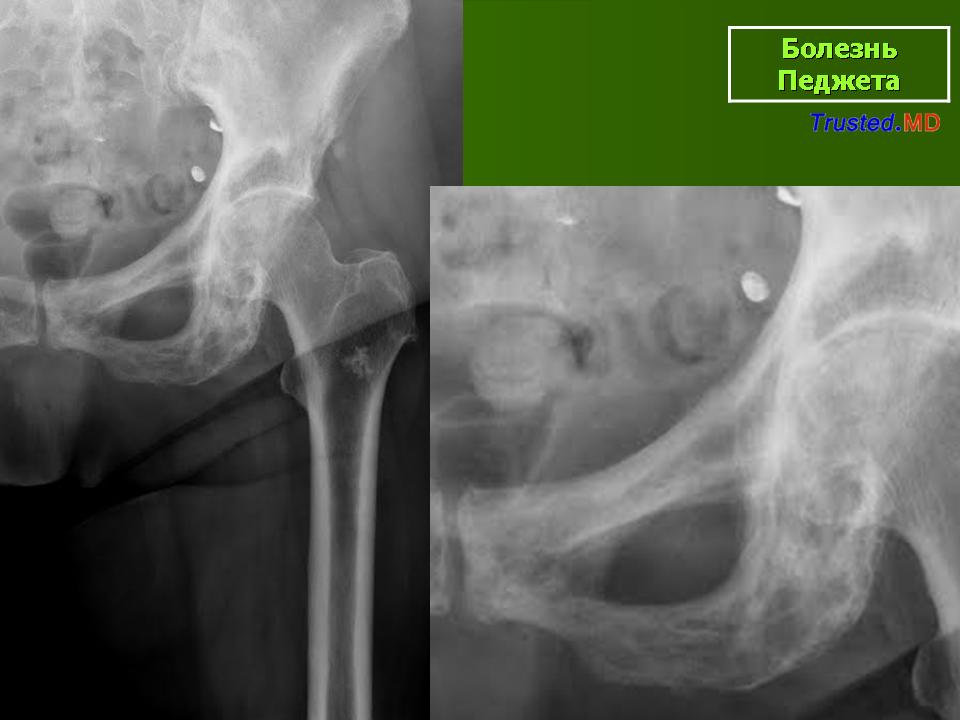

Болезнь Педжета (костей) (деформирующий остеит) ― заболевание, характеризующееся выраженной патологической перестройкой (ремоделированием) кости, при этом первоначально увеличенная резорбция кости сменяется её усиленным дезорганизованным новообразованием, что приводит к формированию чрезмерно васкуляризированной, болезненной, склонной к переломам кости. В результате длительной беспрерывной перестройки в очаге поражения костная ткань приобретает специфическую мозаичную структуру.

Болезнь Педжета проявляется у больных в возрасте старше 40 лет. Заболеваемость варьирует в пределах 0,1–3% населения. У лиц моложе 40 лет частота заболеваемости не превышает 0,5%, у лиц старше 90 лет частота заболеваемости около 10%. Деформирующий остоз чаще встречается у мужчин. Поражение только одной кости (монооссальная форма), преимущественно большеберцовой, бедренной, или таза встречается редко, в 85% в процесс вовлекается множество костей (длинные кости, кости таза, черепа и позвоночника) ― полиоссальная форма. В основном поражаются кости, несущие наибольшую механическую нагрузку (поясничные и крестцовые позвонки, бедренная и большеберцовые кости и др.); характерны поражения костей крыши черепа; из лицевых костей чаще поражаются челюсти.

Деформирующая остеодистрофия (болезнь Педжета) чаще проявляется у мужчин в возрасте 40-60 лет, характеризуется постепенно прогрессирующим утолщением коркового слоя костей с развитием гиперостозов, деформацией, искривлением костей, беспорядочностью их структуры, образованием в них кист; поражаются кости мозгового черепа, позвоночника и длинных трубча­тых костей. Размеры мозгового черепа увеличиваются, наружная пластинка костей свода черепа местами утолщена, гиперостозы чередуются с участка­ми беспорядочного разрежения кости. В связи с деформацией костных от­верстий и каналов основания черепа и межпозвонковых отверстий наруша­ется функция черепных и спинномозговых нервов, возможны расстройства кровообращения. Деформация глазниц обусловливает экзофтальм. Нередко отмечаются признаки внутричерепной гипертензии. Позвонки сплющены; в трубчатых костях сужены костномозговые каналы, возможны патологические переломы костей, при этом линия перелома четкая, ровная, как при переломе очищенного банана («банановый перелом»); усилены физиологические изгибы позвоночника. Процесс может быть относительно ограниченным или распро­страненным. Содержание кальция и фосфора в крови нормально или слегка увеличено, активность щелочной фосфатазы повышена. Предполагается доми­нантный тип наследования с различной экспрессивностью. Описал болезнь в 1877 г. английский хирург J. Paget (1814-1899).

Болезнь Педжета (БП) является довольно распространенным заболеванием во многих европейских странах, США. Оценка распространенности у людей старше 55 лет колебалась от 2% до 5%. Факт, что значительная доля пациентов остаются бессимптомными на протяжении всей их жизни. БП всегда следует рассматривать в дифференциальной диагностике остеосклеротических, а также остеолитических скелетных поражений.

I стадия (литическя) — острая стадия, определяется деструкция кортикального слоя в виде очагов пламени или в форме клина.

II стадия (переходная) – смешанное поражение (остеолиз + склероз).

III стадия (склеротическая) – преобладание склероза с возможной деформацией кости

В монооссальных случаях, частота которых, согласно публикациям, начинается от 10-20% доходя до почти 50%, дифференциальный диагноз может быть гораздо сложнее. В огромном большинстве случаев БП, наличие неоднородных участков костного склероза или остеолиза с искажением трабекулярной архитектуры в сочетании с кортикальным утолщением и фокальным утолщением кости практически патогномоничен для данного заболевания. Бедренная кость является второй наиболее распространенной монооссальной локализацией после таза. В случаях, когда имеется ее дистальное поражение, рентгенологические признаки, характерные для БП, выявляются с меньшей частотой или менее выражены, так что дифференциация с другими процессами, в частности, опухолевыми, может быть затруднена.